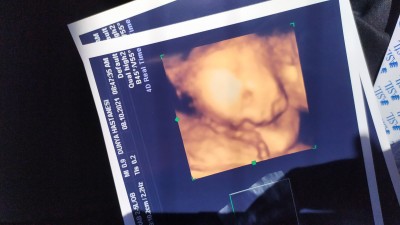

21+3haftadayım detaylı ultrason da bilekten sonraki kısımı göremiyorum demiş sizce varmı Allah rızası için bişeyler diyin

Gebelik haftası 21+3

buda bugunki resimi teyzeleri iki eli de yokmuş parmakları inşallah bi mucize olur büyür ama olmazmış Allah'tan ümit kesilmez inşallah